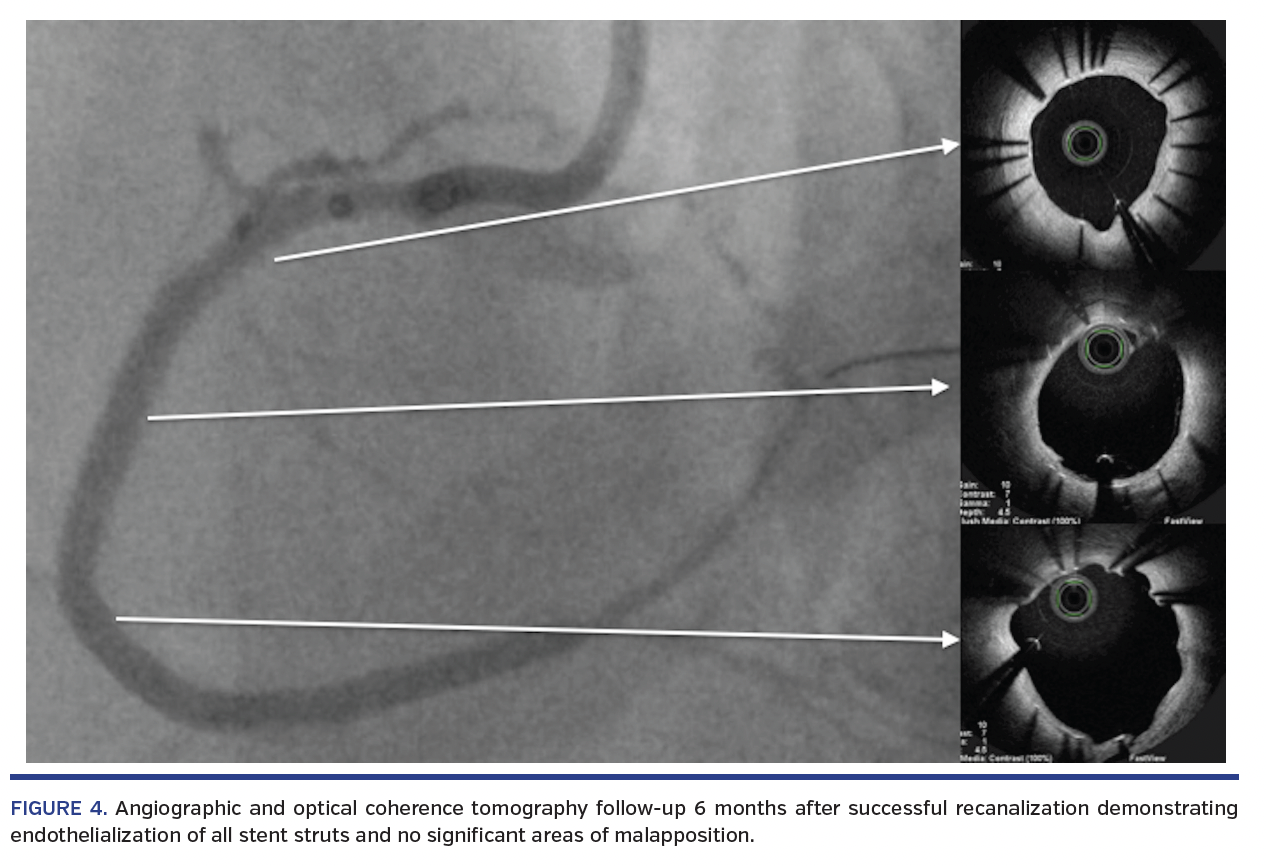

Angiographic and optical coherence tomographic follow-up was performed at 6 months due to the unusual nature of revascularization; it demonstrated a durable result with endothelialization of all stent struts and no significant areas of malapposition (Figure 4). The patient is currently free of angina.